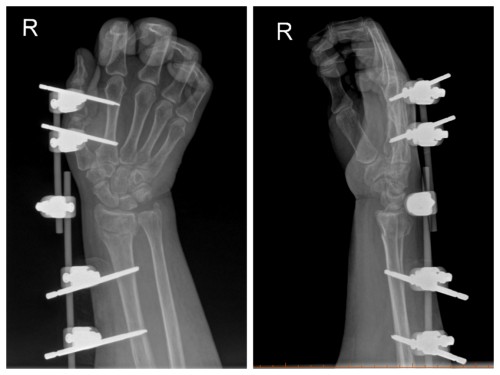

术后

术中,手术团队在患者皮肤上做几个微小切口,精准置入固定针,通过支架的牵引与支撑构建稳定的愈合环境。手术顺利完成,术后1个月患者返院复查时,骨折端已形成明显骨痂。拆除外固定支架后,患者通过科学康复锻炼恢复良好。